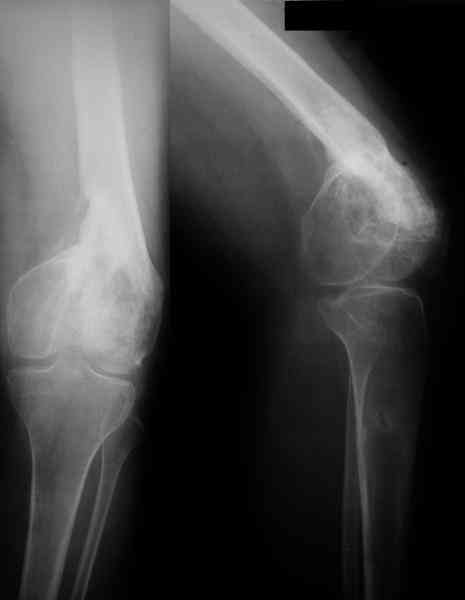

18-летняя девушка получила открытый перелом дистального отдела бедренной кости около 1 года назад.

Лечилась в другом учреждении в АВФ. Сейчас беспокоит укорочение левой ноги до 3 см и ограничение объема движений в коленном суставе 170-120 град). В суставе боли нет.

Для планирования коррекции надо сделать чистый профиль, чтобы сложились мыщелки. Лучше еще сделать два боковых снимка - в крайних положениях

коленного сустава.

В любом случае для правильного планирования необходимы более информативные боковые снимки, вероятно есть ротационное смещение и про него не забудьте.